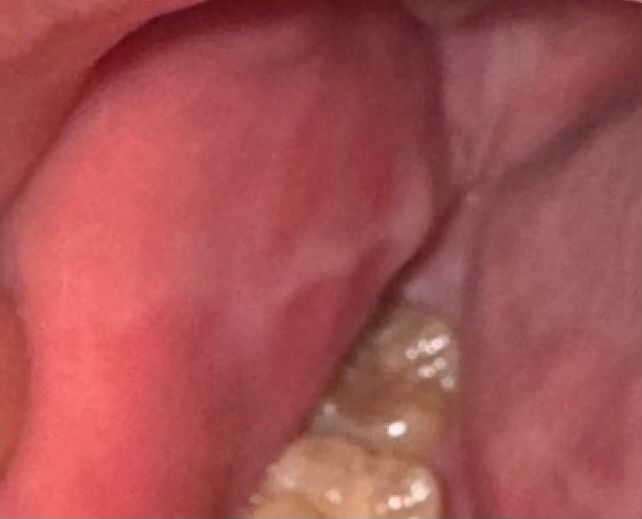

어금니 볼쪽 염증 이게뭘까요? 구강암이랑 관련이 있을까요?

어금니 아래 볼에 저렇게 염증같은게 생겨서 몇주정도 고통받고 있어요

사진상에 보이는건 염증이 아니고 볼이 치아에 씹혀서 그러는거 같습니다. 시간이 지나면 괜찮아 지는거니 너무 걱정하지마세요.

사진에서 보이는 양상은 편평태선의 가능성도 있으나 어금니가 바깥으로 기울어지거나 큰 혀 등의 원인으로 만성적으로 볼을 자주 씹을 경우 생기는 chronic biting, linea alba의 가능성도 있습니다 만약 만성적인 볼 씹힘의 경우 증상이 없다면 치료는 불필요하고 식사 시 볼을 씹지 않도록 습관 개선이 필요합니다. 그래도 증상이 지속된다면 스플린트 등을 착용하거나 교정을 할 수 있습니다.

편평태선의 그물성 병소일 수 있습니다. 정확한 검진을 위해 치과에 내원하시어 검사받아보시기 바랍니다.